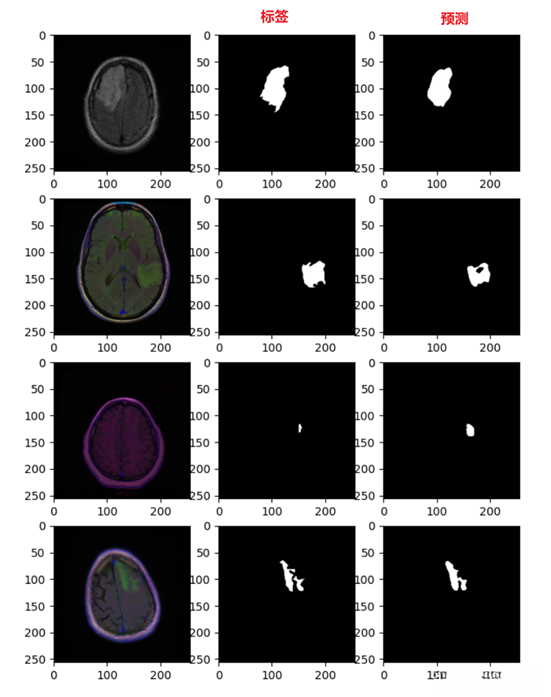

测试

def test():

image, mask = next(iter(dl_test))

image=image.to('cuda')

net = model.eval()

net.to(device)

net.load_state_dict(t.load("./Results/weights/unet_weight/18.pth"))

pred_mask = model(image)

pred_mask=pred_mask

mask=torch.squeeze(mask)

pred_mask=pred_mask.cpu()

num=4

plt.figure(figsize=(10, 10))

for i in range(num):

plt.subplot(num, 4, i*num+1)

plt.imshow(image[i].permute(1,2,0).cpu().numpy())

plt.subplot(num, 4, i*num+2)

plt.imshow(mask[i].cpu().numpy(),cmap='gray')#标签

plt.subplot(num, 4, i*num+3)

plt.imshow(torch.argmax(pred_mask[i].permute(1,2,0), axis=-1).detach().numpy(),cmap='gray')#预测

plt.show()

if __name__ == "__main__":

test()

模型分割效果